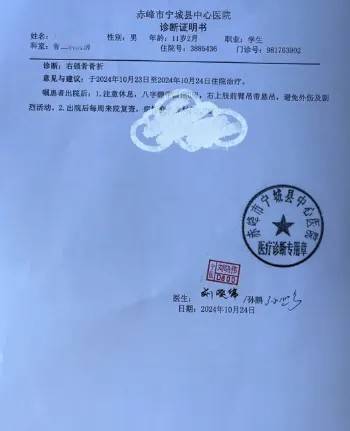

皇冠信用网代理登3(www.hgty.us)为您提供皇冠登录,皇冠盘代理、会员皇冠信用网代理开户、皇冠会员开户业务 10月23日,内蒙古赤峰市宁城县苏木皋小学一学生被老师打伤致锁骨骨折皇冠信用盘结算日是哪天。10月31日,家长贾女士给生活报记者打来电话称,事件已经过去一周时间了,但是校方还没有到医院给孩子道歉,且涉事教师还在上班。

10月30日,内蒙古自治区赤峰市宁城县苏木皋小学一学生家长贾女士给记者打来电话,介绍了孩子被打的原因皇冠信用盘结算日是哪天。贾女士称,放学通道的墙上有一个电灯的开关,好多孩子放学时都随手去拨弄开关。出于安全考虑,学校和老师都禁止孩子拨弄开关。23日放学时,他儿子和另一个同学调皮,再去拨弄了那个开关,被正在值班的另一个班的班主任发现,把她儿子打了,且打骨折了。

图片由报料者提供